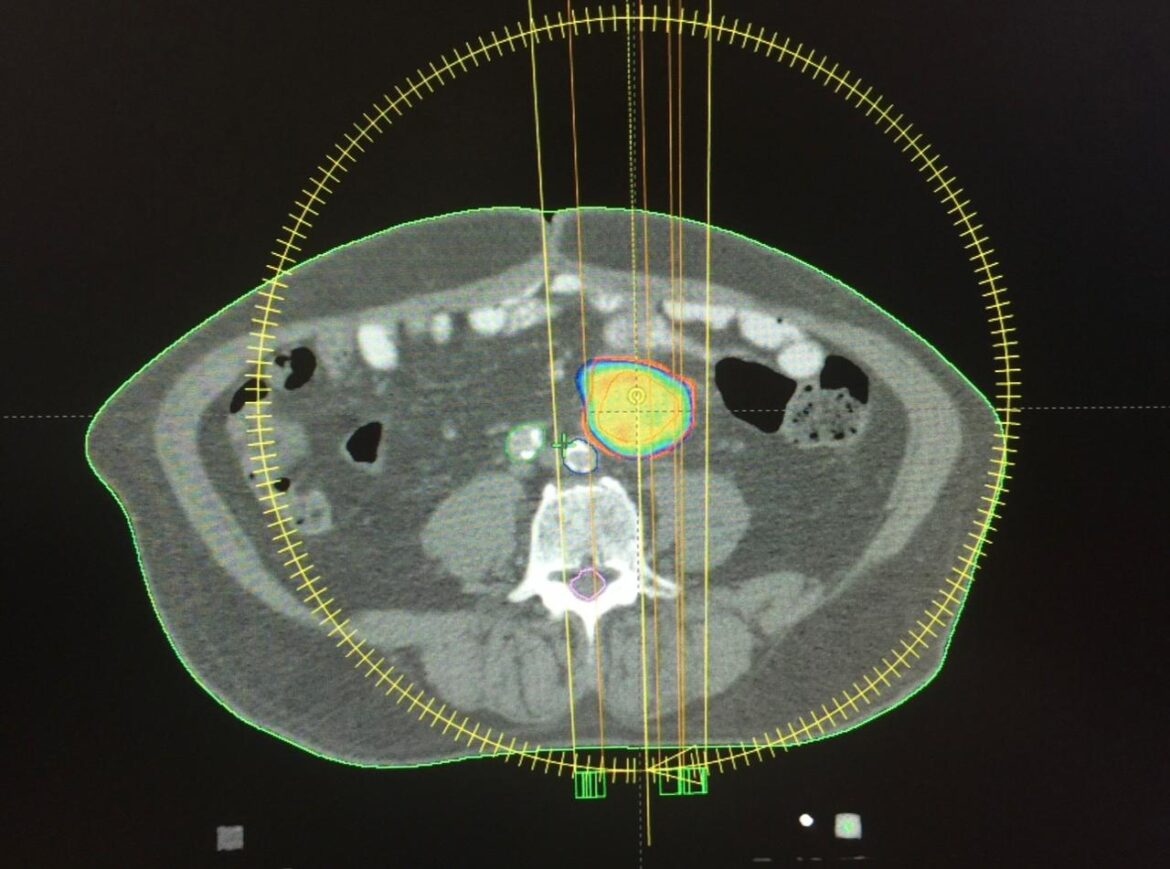

En 2015, especialistas del HOMS practicaron de manera exitosa la primera técnica de radiocirugía extracraneal, con avanzada tecnología en su Centro del Cáncer.

La práctica se realizó en un paciente con metástasis ganglionar de primario colorrectal, utilizando PET-CT y tomografía de abdomen y pelvis con doble contraste, fusión de ambas imágenes y posterior verificación antes del tratamiento, mediante imágenes tomográficas del blanco a tratar.